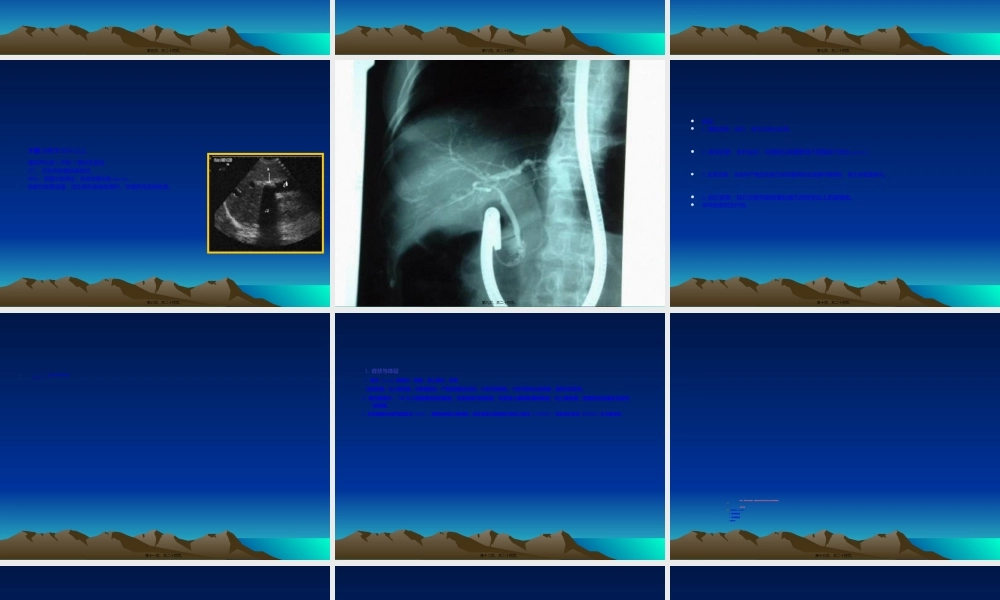

胆道感染胆道感染(gǎnrǎn)(gǎnrǎn)及及胆石病胆石病广州中医药大学第一广州中医药大学第一(dìyī)(dìyī)附属医院肝胆外科附属医院肝胆外科王百林副教授医学博士王百林副教授医学博士第一页,共二十四页。主要内容1.解剖(jiěpōu)生理2.诊断检查方法3.胆道感染的诊治4.胆石病的诊治第二页,共二十四页。一.一般概况(gàikuàng)1.外科常见病,发病趋势,逐年增高,发病居外科急腹症第二位。2.胆道:胆囊、胆总管、肝总管和肝胆系统。3.感染和结石:胆囊炎、胆管炎;结石:胆囊结石、肝内胆管结石和肝外胆管结石第三页,共二十四页。1.胆道系统解剖⑴.胆囊:分底、体、颈、管。⑵.胆囊三角(calottriangle):肝下缘、胆囊管与肝总管围成的三角形区域。前哨淋巴结,和胆囊动脉通过。⑶.肝胆管(dǎnguǎn)系统:左、右肝管(一级)、肝叶胆管(dǎnguǎn)(二级)、肝段胆管(dǎnguǎn)(三级)和肝外周区域胆管(dǎnguǎn)或次胆管(dǎnguǎn)。⑷.肝外胆管系统:肝总管、胆总管和壶腹部构成。⑸.肝外胆道的血管:胃十二指肠动脉的分支,胆囊动脉一般起自肝右动脉的分支。第四页,共二十四页。1.胆汁:肝内形成,胆囊储存。2.胆囊的功能(gōngnéng):吸收、分泌和运动功能(gōngnéng)。3.胆汁的排放:与肝脏的分泌压、胆囊收缩和胆总管末端的括约肌协调作用及十二指肠的运动有关。第五页,共二十四页。1.实验室检查:血常规、肝功能、尿常规、出凝血时间和淀粉酶检查2.十二指肠引流:经口腔或鼻导管注入33%硫酸镁后根据不同的时间引流胆汁进行检查。3.X线检查:⑴胆系平片:阴性(yīnxìng)结石(胆固醇),阳性结石(含钙量多)。第六页,共二十四页。⑵口服胆囊造影或静脉胆道造影:口服碘番酸通过胆囊代谢(dàixiè)。静脉注射泛影葡胺可显示胆道系统的形态。联合应用效果更好。⑶经皮肝穿刺胆道造影(PTC):或PTCD.在肝功能障碍或胆红素大于2MG时可采用。⑷经十二指肠镜逆行胰胆管造影(ERCP)。有并发胆道感染和胰腺炎的可能,可放置鼻胆管引流。⑸术中胆道造影:可了解胆道情况。⑹术中胆道镜:可了解术中情况。第七页,共二十四页。B超诊断率95%以上强回声光团+声影+移动性首选CT、对实体肿瘤效果较好。MRI、胆囊功能测定。胆道成像检查(jiǎnchá)。放射性核素显像:对功能性疾病效果好,对器质性疾病较差。第八页,共二十四页。第九页,共二十四页。•病因•1.梗阻因素:结石、寄生虫和炎症等。•2.感染因素:多种途径,但梗...

1、当您付费下载文档后,您只拥有了使用权限,并不意味着购买了版权,文档只能用于自身使用,不得用于其他商业用途(如 [转卖]进行直接盈利或[编辑后售卖]进行间接盈利)。

2、本站所有内容均由合作方或网友上传,本站不对文档的完整性、权威性及其观点立场正确性做任何保证或承诺!文档内容仅供研究参考,付费前请自行鉴别。